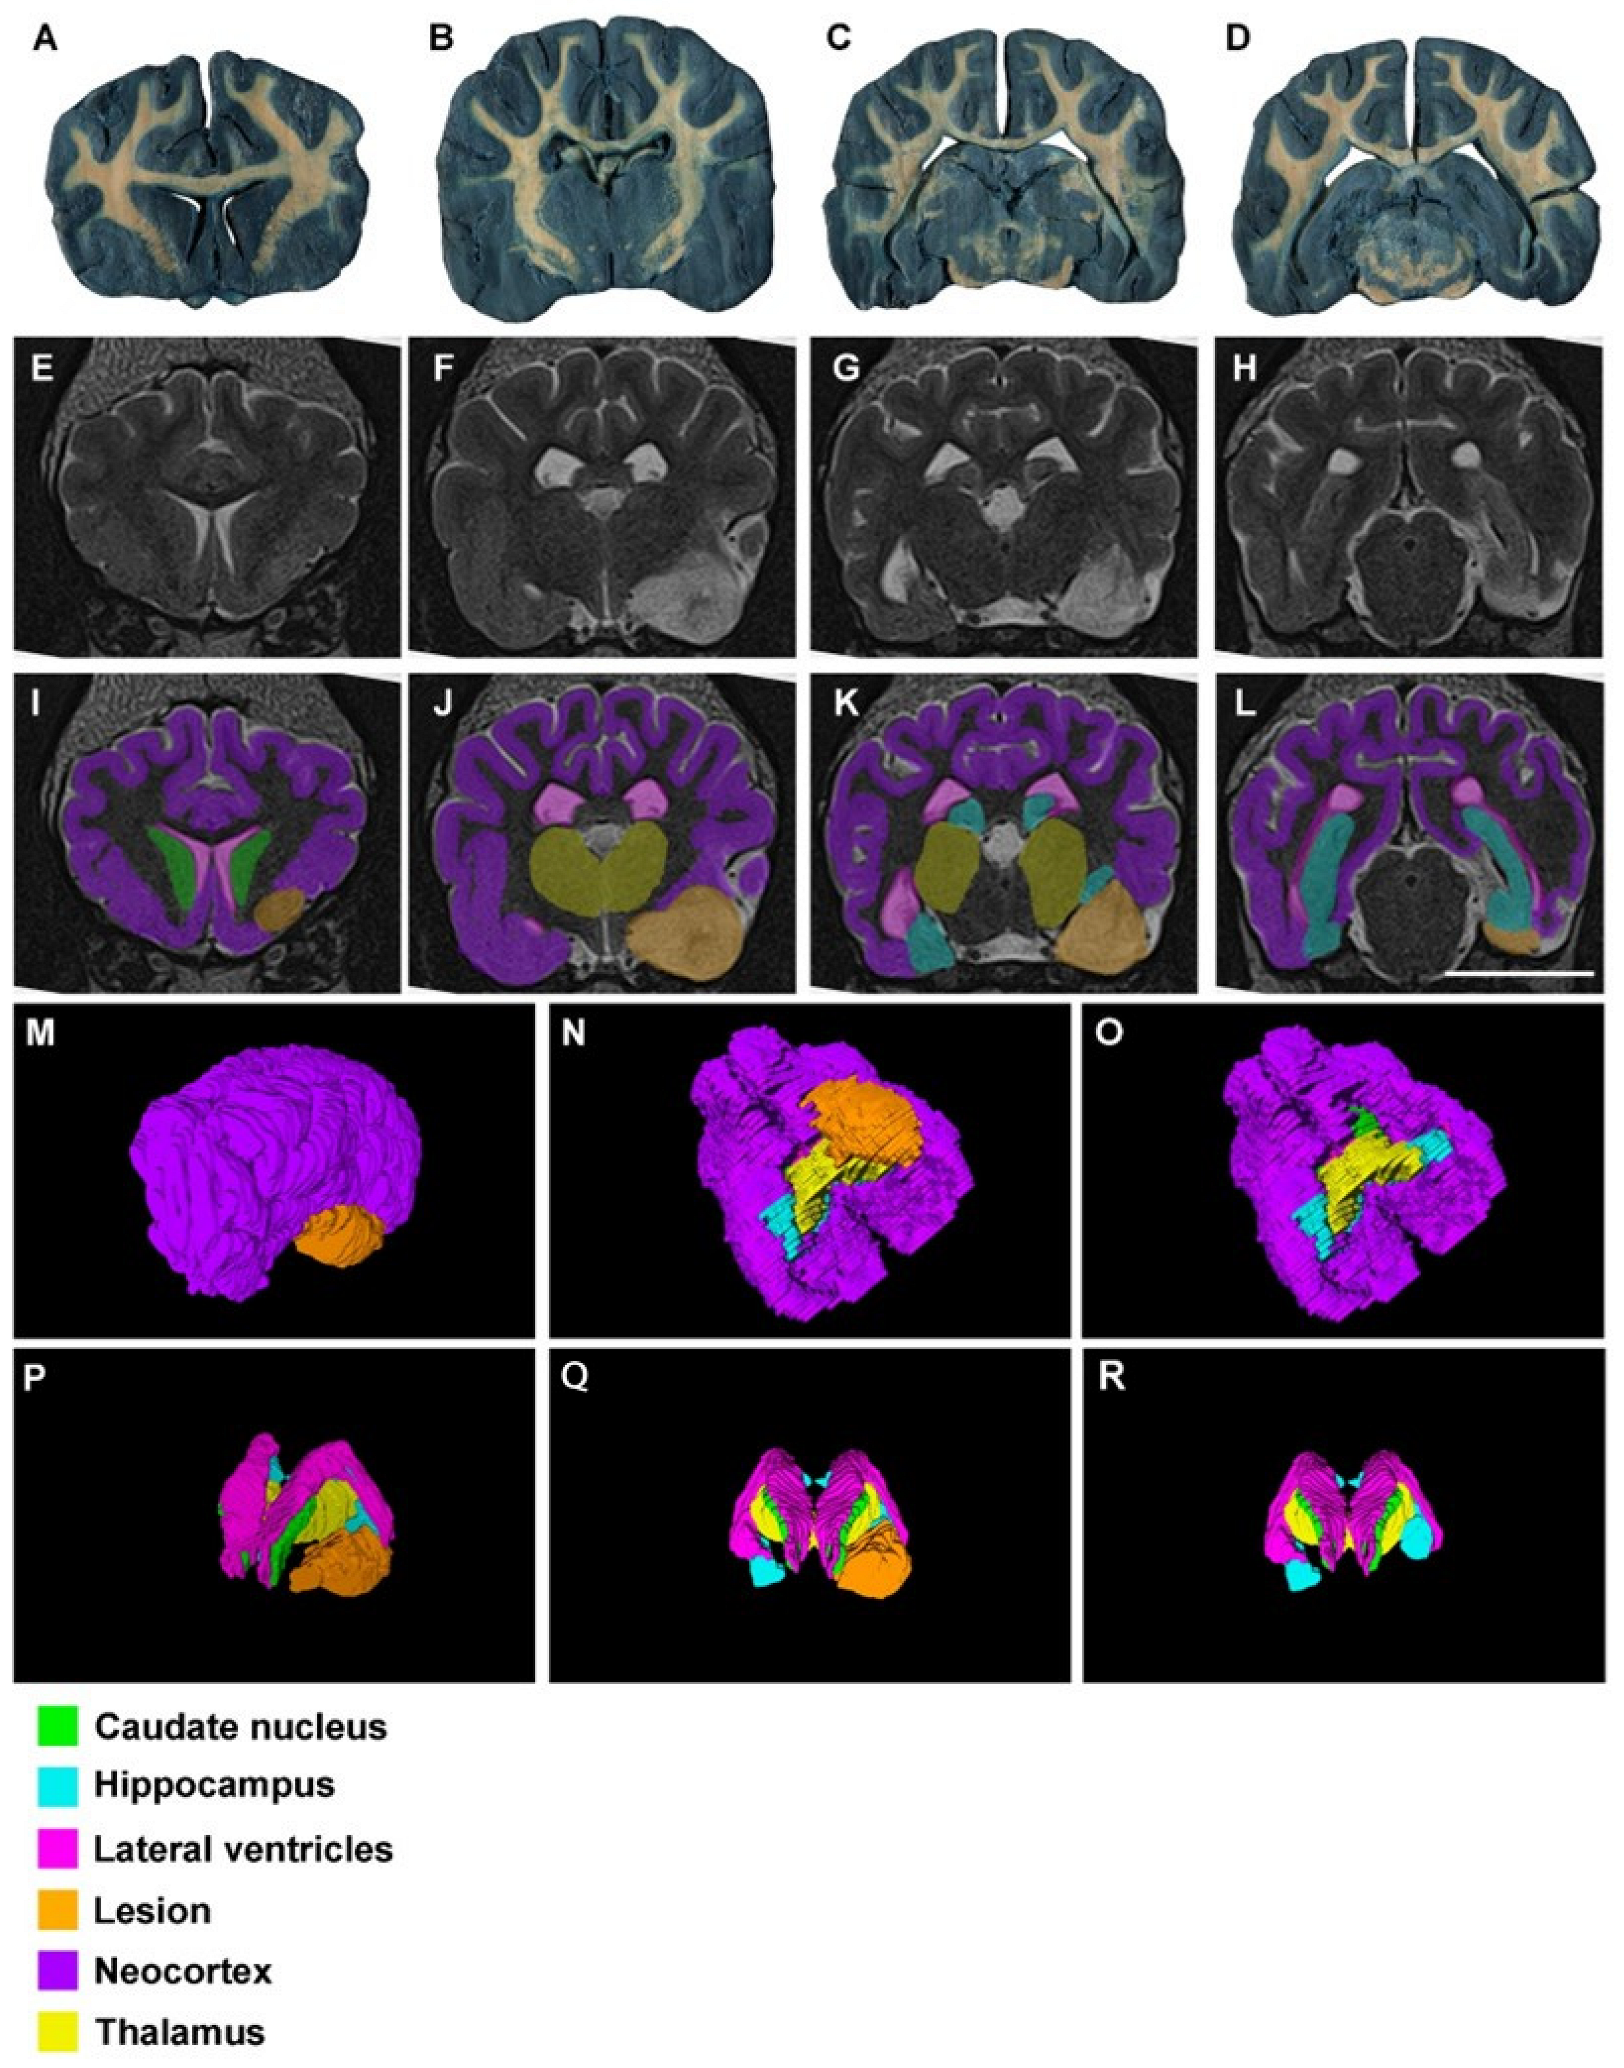

3. Results